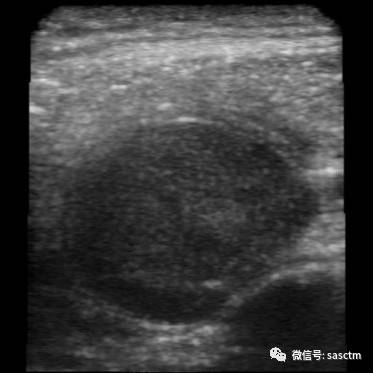

当他按照说明书用iPhone式超声检测仪检查自己的颈部时,在iPhone屏上清晰地显示了一个3公分大小的高密度区(下图)。他不是肿瘤专科医生,但他的直觉让他感觉到那是一个肿块。进一步的病理活检确定了该肿块是一鳞状细胞癌!

Dr.Martin用iPhone超声仪判断出自己可能患癌了